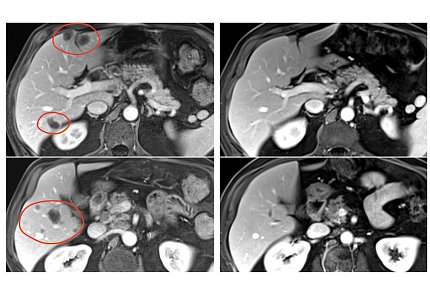

Photo: NCI

In the third phase, 34 patients received pembrolizumab immediately before selected TIL therapy to prevent the newly introduced immune cells from becoming inactivated by the patient’s own immune system. This group had the best response.

In the trial’s second and third phases, objective responses were seen in multiple types of gastrointestinal cancers, including cancers of the colon, rectum, pancreas and bile duct. Responses lasted between 8 months and more than 5.8 years in the group that received selected TIL therapy alone, and between 4 months and 3.5 years in the group that received selected TIL therapy and pembrolizumab. Serious side effects occurred in 30% of patients treated with selected TILs.